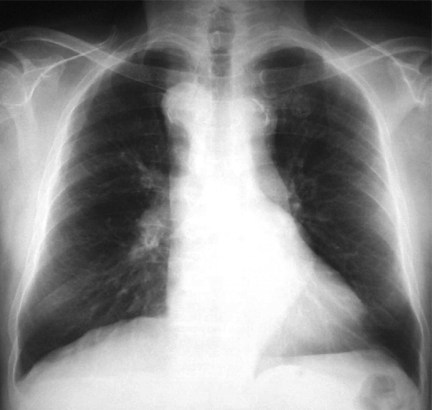

Vascular Slings and Rings:

Now these are rare! Congenital anomalies of the aortic arch and pulmonary artery can cause anomalous vessels to constrict the trachea or oesophagus. These manifest in a stridor from birth which becomes exaggerated during a respiratory tract infection. CT angiography and bronchoscopy are used to evaluate them. These kids need surgery as their definitive treatment.

Eg of a Double Aortic Arch causing tracheal compression: